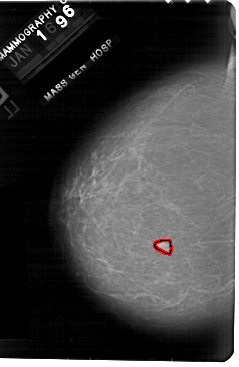

A_1869_1.RIGHT_CC

LEFT_CC LINES 5491 PIXELS_PER_LINE 3571 BITS_PER_PIXEL 12 RESOLUTION 43.5 OVERLAY

FILE: A_1869_1.LEFT_CC.OVERLAY

TOTAL_ABNORMALITIES 1

ABNORMALITY 1

LESION_TYPE MASS SHAPE IRREGULAR MARGINS ILL_DEFINED

ASSESSMENT 4

SUBTLETY 3

PATHOLOGY BENIGN

TOTAL_OUTLINES 1

BOUNDARY